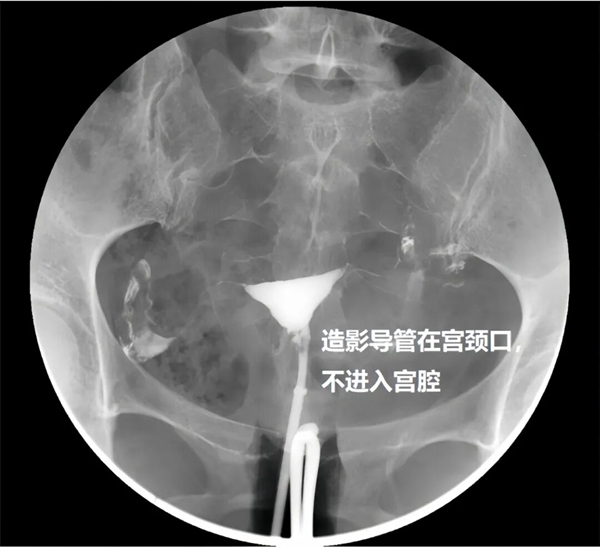

與傳統(tǒng)無(wú)痛技術(shù)不同,該技術(shù)并非依賴麻醉,而是通過(guò)檢查方式的革新實(shí)現(xiàn)無(wú)痛體驗(yàn)。無(wú)痛子宮輸卵管造影是在傳統(tǒng)造影基礎(chǔ)上,采用新型專用導(dǎo)管,無(wú)需插入宮腔,僅在宮頸外口利用外界壓力即可完成含碘造影劑的注入,從根本上避免了導(dǎo)管對(duì)宮腔的刺激。

其二,精準(zhǔn)成像,診斷更可靠。導(dǎo)管不進(jìn)入宮腔,避免了宮腔內(nèi)遮擋與阻礙,能更清晰、準(zhǔn)確地呈現(xiàn)子宮腔形態(tài)與輸卵管通暢情況,為臨床診斷提供更精準(zhǔn)的影像依據(jù);